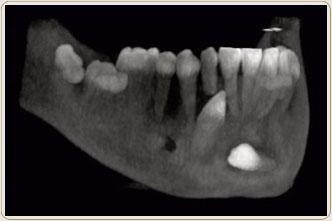

6、埋伏牙必须拔除。埋伏牙多是在口腔健康中才会发现,大多数埋伏牙生长不会被看到或者感知到,一旦发现尽快拔除,以免造成不必要的危险。